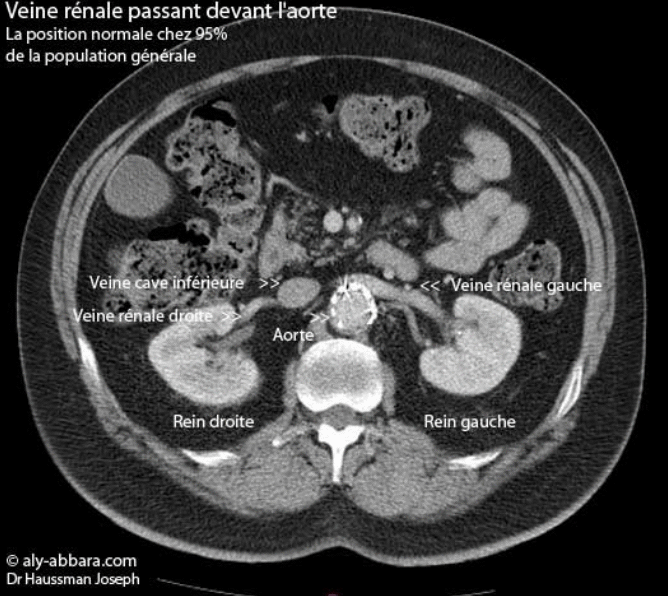

Veine rénale gauche en position antéro-aortique

(Scanner abdominal chez un individu âgé de 50 ans)

Il s'agit de la position anatomique la plus fréquente de la veine rénale gauche (chez 95 % de la population générale).

Cette veine et en position rétro-aortique chez 5 % de la population générale.

Imagerie et diagnostic réalisés par Dr Haussman Joseph. Extraction des images,

légendes, animation et publication par Dr Aly Abbara.